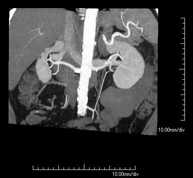

Prova diagnòstica no invasiva que consisteix en l'estudi de l'artèria aorta abdominal a través de l'obtenció d'imatges d'alta definició anatòmica mitjançant l'ús d'un equip de TC (Tomografia Computeritzada) i de contrast iodat. La qualitat de les imatges permet realitzar reconstruccions en 2D i 3D gràcies a estacions de treball especialitzades en l'estudi arterial. Està indicat en aquells pacients amb malaltia vascular (arteriosclerosi), en aneurismes d'aorta, en pacients amb dolor abdominal de possible origen vascular, en estudis prequirúrgics de lesions adjacents a l'aorta abdominal com a "mapa" vascular. La informació obtinguda de manera no invasiva és indispensable per als pacients que requereixen tractament percutani o quirúrgic. En aquells pacients que només requereixen seguiment de les lesions vasculars, aquesta tècnica és la tècnica no invasiva d'elecció juntament amb l'angio-RM. - Angio-TC Artèries renals

Prova diagnòstica no invasiva que consisteix en l'estudi de les artèries renals a través de l'obtenció d'imatges d'alta definició anatòmica mitjançant l'ús d'un equip de TC (Tomografia Computeritzada) i de contrast iodat. La qualitat de les imatges permet realitzar reconstruccions en 2D i 3D gràcies a estacions de treball especialitzades en l'estudi arterial. Està indicat en aquells pacients amb malaltia vascular (arteriosclerosi), en aneurismes d'aorta, en pacients amb dolor abdominal de possible origen vascular, en estudis prequirúrgics de lesions adjacents a l'aorta abdominal com a "mapa" vascular. La informació obtinguda de manera no invasiva és indispensable per als pacients que requereixen tractament percutani o quirúrgic. En aquells pacients que només requereixen seguiment de les lesions vasculars, aquesta tècnica és la tècnica no invasiva d'elecció juntament amb l'angio-RM. - Angio-TC Aorto-ilíac

Prova diagnòstica no invasiva que consisteix en l'estudi de l'artèria aorta abdominal amb l'obtenció d'imatges d'alta definició anatòmica mitjançant l'ús d'un equip de TC (Tomografia Computaritzada) i contrast iodat. La qualitat de les imatges permet realitzar reconstruccions en 2D i 3D gràcies a estacions de treball especialitzades en l'estudi arterial. Està indicat en aquells pacients que pateixen malaltia vascular (arteriosclerosi), aneurismes d'aorta, en pacient amb dolor abdominal d'un possible origen vascular, en estudis prequirúrgics de lesions adjacents a l'aorta abdominal com el "mapa" vascular, etc. La informació obtinguda de forma no invasiva és indispensable per als pacients que requereixen tractament percutani o quirúrgic. En aquells pacients que només requereixen un seguiment de les lesions vasculars, aquesta tècnica és la tècnica no invasiva d'elecció juntament amb l'angio RM. - Angio TC d'artèries renals

Prova diagnòstica no invasiva que consisteix en l'estudi de les artèries renals amb l'obtenció d'imatges d'alta definició anatòmica mitjançant l'ús d'un equip de TC (Tomografia Computaritzada) i contrast iodat. La qualitat de les imatges permet realitzar reconstruccions en 2D i 3D gràcies a estacions de treball especialitzades en l'estudi arterial. Aquesta prova està indicat en aquells pacients que pateixen HTA refractària al tractament, en pacients amb lesions renals que tenen un mapa vascular prequirúrgic, etc. - Angio TC d'aorta-ilíaca